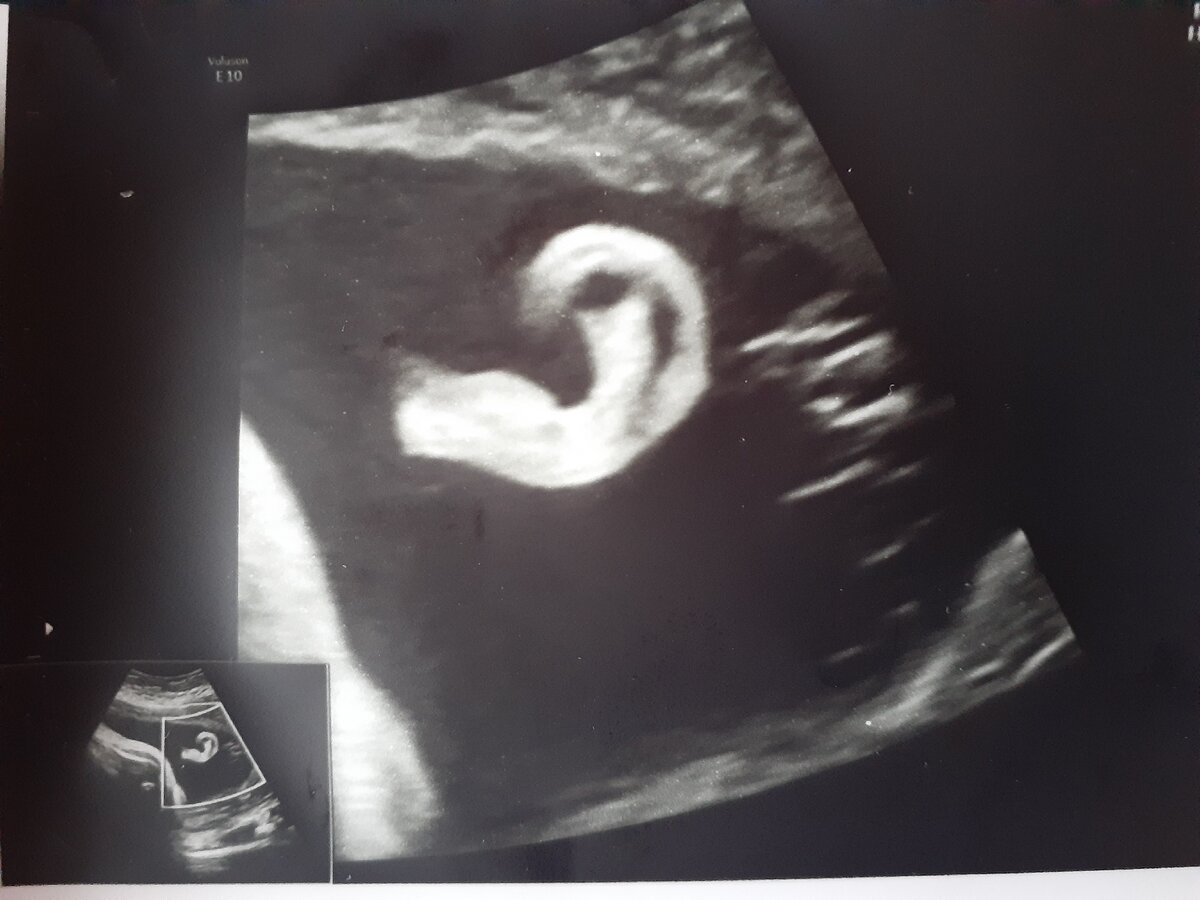

Чем может заниматься ребенок в утробе матери - 7 месяц

И уже 7 месяц, уже приличные габариты живота, да и сам ребенок весит порядка 2300 грамм (мы идем с опережением на 300-500 грамм от нормы). Крупный плод, вот.

Но оказывается счастье кроется внутри! Я ходила на три скрининга и если на первых двух, ребенок вел себя тихо, более менее не так активно, то на третьем скрининге это нечно.

Врач показала, что дите само себя развлекает и по полной программе.

Во-первых, это активность! Малышка при своих приличных 2-х кило двигает ручками, ножками, хоть и очень все это в ограниченном пространстве.

Во-вторых, ребенок, ручкой уже способен трогать свое лицо. Прикасается к носу, губам, теребит ушко.

В третьих, она ручками берет пуповину и начинает с ней играть, то нагребет ее вокруг себя, то отпустит.

В четвертых, ребенок уже прекрасно слышит. Все голоса, которые раздаются возле нее. Таким образом, если к ней подходят старшие дети, начинают, что-то кричать, говорить, смеятся, плакать она все это слышит и начинает у себя там двигаться активно.